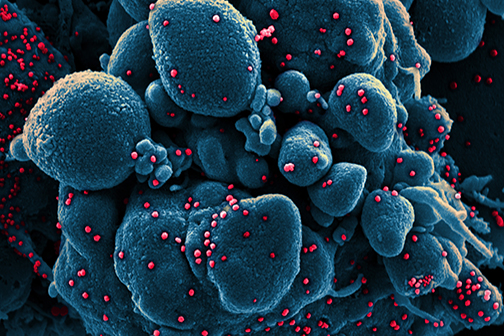

LSU Health New Orleans Study Reports Compound Blocks SARS-CoV-2 and Protects Lung Cells

Research conducted at LSU Health New Orleans Neuroscience Center of Excellence reports that Elovanoids, bioactive chemical messengers made from omega-3 very-long-chain polyunsaturated fatty acids discovered by the Bazan lab in 2017, may block the virus that causes COVID-19 from entering cells and protect the air cells (alveoli) of the lung. More